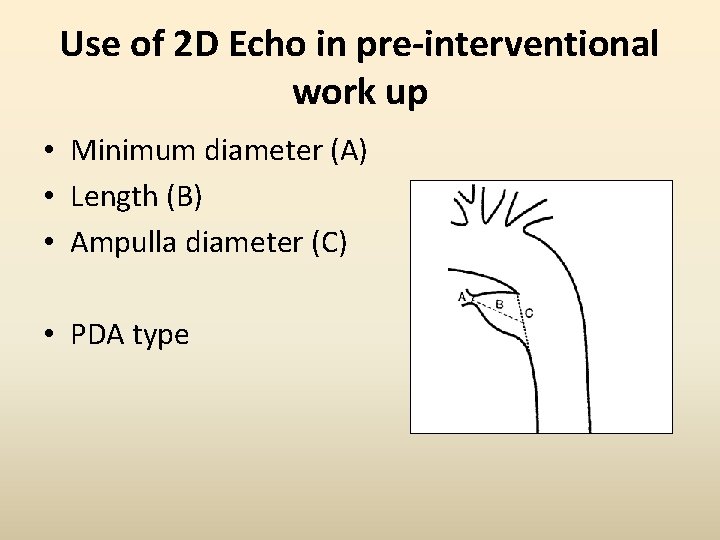

Use of 2 D Echo in pre-interventional work up • Minimum diameter (A) • Length (B) • Ampulla diameter (C) • PDA type

Use of 2 D Echo in pre-interventional work up • Echo classification corresponding to Krichenko’s A- Conical with a narrow pulmonary end B- Short with narrow aortic end C- Tubular without constriction D- Multiple constrictions E- Long and tortuous requiring >1 echo plane for complete imaging Comprehensive Assessment of Patent Ductus Arteriosus by Echocardiography Before Transcatheter Closure. J Am Soc Echocardiogr 2002; 15: 1154 -9.

Important to define the Ampulla • Adequate Ampulla: Length of PDA> Narrowest portion of the PDA (usually at pulm end)

• Inadequate ampulla: Short PDA - Worst example : WINDOW type (Type B)

• Tubular ductus: Same diameter from aorta to pulmonary end

Echo classification • CONICAL DUCT ( common) • WINDOW DUCT • TUBULAR DUCT

Correlation of 2 D echo and Angio • Wong et al found poor correlation between colour Doppler and angiographic measurements 1 • 2 DE imaging overestimates the minimal diameter in comparison with angiography but in the majority difference was <1 mm 2 • In ~14% there is discrepancy in classification type 2 • Ampulla and length measurement were the most discordant 1. Wong et al. Validation of color Doppler measurements of minimum patent ductus arteriosus diameters: significance for coil embolization. Am Heart J 1998; 136: 714 -7. 2. Comprehensive Assessment of Patent Ductus Arteriosus by Echocardiography Before Transcatheter Closure. J Am Soc Echocardiogr 2002; 15: 1154 -9.